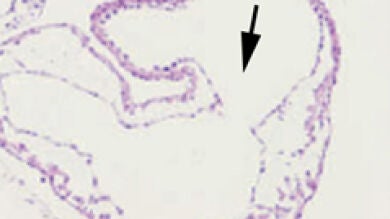

Sus análisis muestran que en estos ratones la adición de los precursores al tubo cardiaco es anormal, provocando un acortamiento de los polos. Además, la formación de las válvulas cardiacas es defectuosa. Los resultados obtenidos, explica Sanz Ezquerro, demuestran que “Arid3b controla la arquitectura y el movimiento de las células progenitoras, en parte regulando la expresión de otros genes y que Arid3b es esencial para el desarrollo embrionario del corazón”.